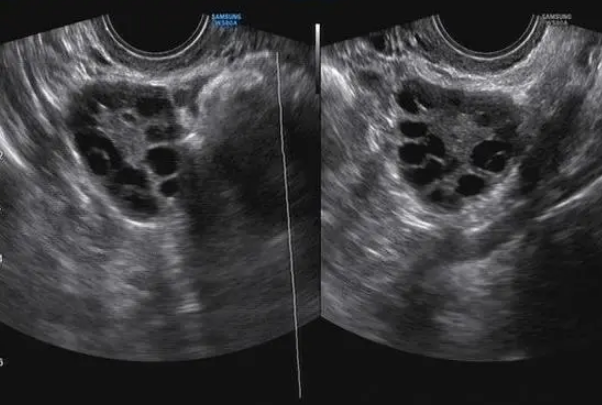

促排期间B超监测到卵泡较多医生可以控制取卵数量吗?

问题描述: 我现在已经进入了试管促排阶段,今天去做B超监测的时候,发现我卵泡比较多,之前我听其他做试管的姐妹说,卵泡数量不是越多越好的,一旦数量太多很有可能导致卵泡质量下降进而降低试管的成功率,心里很担心,想问问大家去医院的话医生在做取卵手术之前,可以控制这个数量吗?

卵泡多医生可以控制取卵数量,根据B超监测的结果,医生可以适当增减促性腺激素的剂量,以精细调控卵泡的发育速度和数量,如果卵泡发育过快或数量过多,可能会建议暂时停止使用促性腺荷尔蒙,等待部分卵泡自然消退。还可以在取卵过程中,医生可以选择性地仅取出部分成熟的卵泡,而将其余卵泡留待自然周期中成熟。

尽管促排的目的是获取多个卵泡,但过多的卵泡可能会增加OHSS的风险,或者导致卵子质量下降。因此,在某些情况下,医生可能需要采取措施来控制取卵数量。这可以通过以下方式实现:

1. 个体化治疗方案:每位患者的身体状况和反应对药物的刺激都是不同的。因此,制定个体化的治疗方案对于控制取卵数量至关重要。医生会根据患者的年龄、基础卵泡数目、以往的治疗反应以及激素水平等因素,来调整药物剂量和使用时间;

2、早期停止促排卵治疗:如果超声检查显示卵泡数量过多或者是发育的过于快速,医生可能会建议提前停止促排卵药物的使用,以避免过多的卵泡发育;

3、选择性取卵:在取卵过程中,医生可以选择只取部分成熟的卵泡,留下一些未成熟的卵泡,以减少OHSS的风险;

4、调整药物剂量:医生可能会根据患者的反应和荷尔蒙水平调整促排卵药物的剂量,以减少卵泡的数量;

5、定期监测和评估:在整个COH过程中,医生会定期进行血液检测和超声检查,以监测卵泡的发育情况和患者的身体反应。这些监测数据帮助医生评估患者对治疗的反应,并及时调整治疗方案。

综上,控制取卵数量不仅关系到患者的健康和安全,也影响着辅助生殖技术的成功率。通过以上等方法,医生可以有效地控制取卵数量,从而提高治疗的安全性和成功率。这些方法的应用需要医生的专业知识和经验,同时也需要患者的信任和合作。